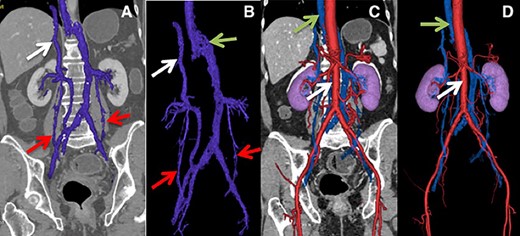

A 73-year-old female patient with no relevant history, upper and lower endoscopies were performed due to dyspepsia, biopsies of an anal lesion reported a neuroendocrine carcinoma, in order to stage the malignancy, CT of the abdomen and pelvis revealed a lymphatic mass in front of the sacrum and presence of an anatomical variant of the left IVC, which continues with the azygos vein to the right of the thoracic spine. (Fig. 3).

(A) Lower arrows show ovarian veins, upper arrow shows hypoplastic suprahepatic segment of the IVC. (B) Lower arrows show ovarian veins, right upper arrow shows hypoplastic suprahepatic segment of the IVC, left upper arrow shows azygos vein. (C and D) Lower arrow shows aorta, upper arrow shows azygos vein.